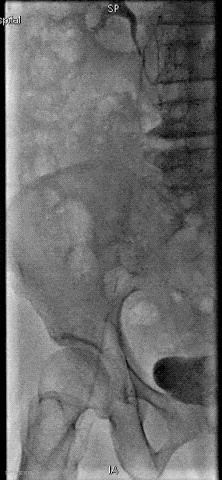

手术过程

抽吸结果